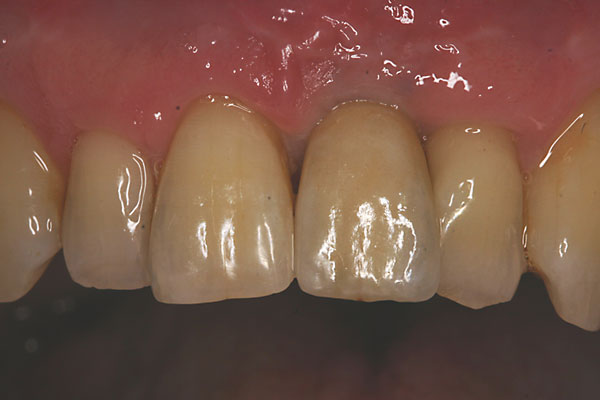

Fall: Einzelzahnlücke nach Zahnextraktion